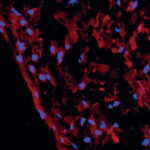

Attuali protocolli nel trattamento del tumore odontogeno cheratosico (cheratocisti): revisione della letteratura

Riassunto

La cheratocisti odontogena, dal 2005 classificata dall’Organizzazione Mondiale della Sanità come tumore odontogeno cheratosico, è una lesione benigna, localmente aggressiva, con un’alta tendenza alla...